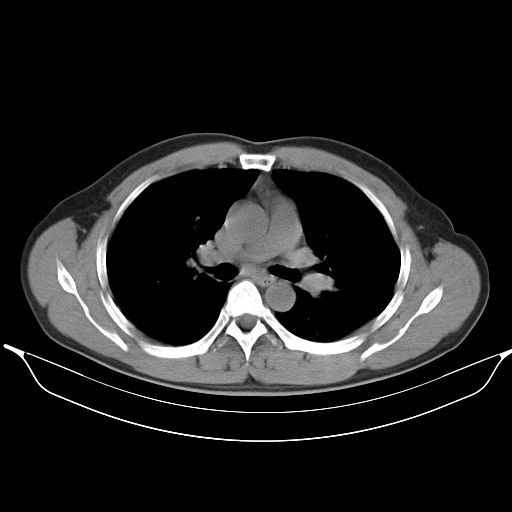

标题: CT25490:男,40岁,体检发现;无其它不适。 [打印本页]

标题: CT25490:男,40岁,体检发现;无其它不适。

考虑右下肺周围性肺癌并肺内多发转移,纵隔淋巴结转移!

支持 !考虑右下肺周围性肺癌并肺内多发转移,纵隔淋巴结转移,(气管前腔静脉后,隆突下,主动脉弓下都有了)